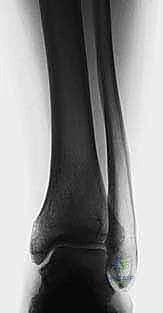

1. التخطيط الجراحي الدقيق (Pre-operative Planning)

يتم إجراء صور أشعة سينية خاصة (طويلة للساق بالكامل أثناء الوقوف) وأشعة مقطعية (CT Scan) ثلاثية الأبعاد. يقوم الدكتور محمد هطيف باستخدام برامج حاسوبية متقدمة لحساب الزاوية الدقيقة للتشوه، وتحديد حجم "الوتد العظمي" (Bone Wedge) الذي يجب إزالته أو إضافته لإصلاح المحور.

• المرحلة الثانية (الأسابيع 3 - 6): بدء تمارين المدى الحركي (تحريك الكاحل لأعلى وأسفل) لمنع التيبس. يتم متابعة التئام العظم بالأشعة.

• المرحلة الثالثة (الأسابيع 6 - 12): بمجرد ظهور علامات التئام العظم في الأشعة، يُسمح بالتحميل الجزئي للوزن تدريجياً، وصولاً إلى التحميل الكامل. تبدأ تمارين تقوية العضلات المحيطة بالكاحل.